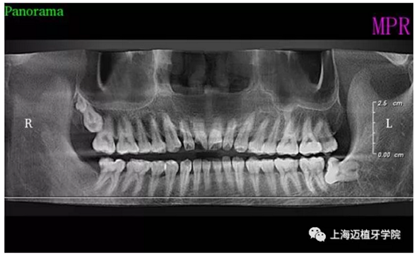

術(shù)前全景片

主訴:前門(mén)外傷牙根折要求修復(fù)?現(xiàn)病史:前門(mén)牙外傷,劈裂至根部,無(wú)法固定及其他修復(fù),要求種植?檢查:11牙冠2/3缺損,唇腭向劈裂,唇部紅腫。 CT示根折, 骨寬度9.47mm,距鼻底12.34mm,Ⅲ類骨。 口腔衛(wèi)生一般